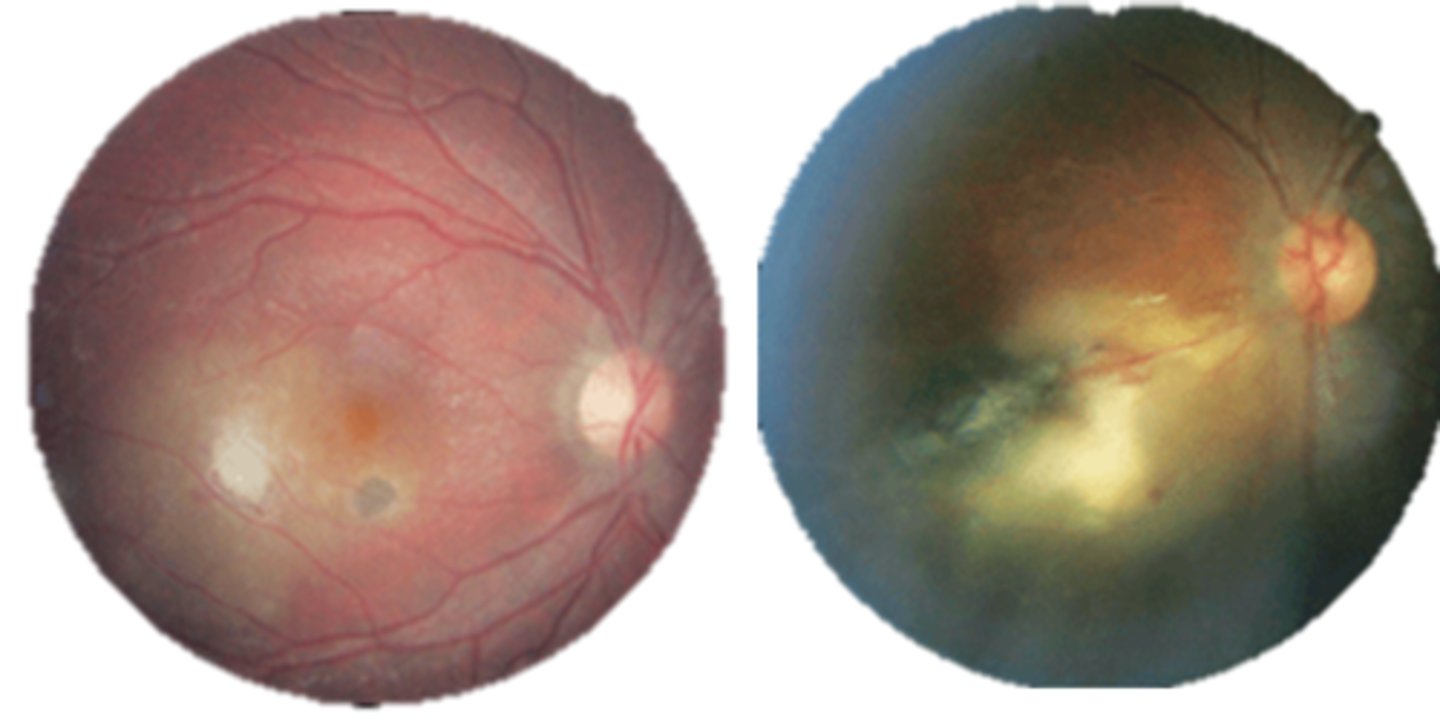

What finding of toxoplasmosis is seen in A/B?

retinitis turns into hazy scar with nerve pallor

What finding of toxoplasmosis is seen in C/D?

scarring overtime with VA loss/scotoma